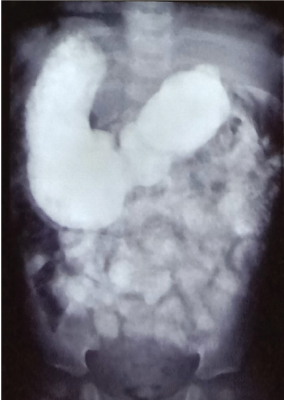

Plain chest and abdominal X-ray showed dextrocardia with higher level of left hemi diaphragm with gastric fundal air on right side (Fig. 1). Two-dimensional echocardiography showed situs inversus, dextrocardia with normal ventricular function with no other cardiac anomaly. Ultrasonography (USG) of abdomen revealed liver on left side with situs inversus and bilobed spleen on right side. Due to obscured gases pancreas was not clearly visualized. The proximal part of superior mesenteric artery and superior mesenteric vein were visualized on color Doppler. USG abdomen of both parents showed situs solitus. Upper gastro intestinal contrast was study done with non-ionic contrast which revealed gastro-esophageal junction and gastric fundus was located on right side of spine with pylorus, duodenum located on left side of spine with grossly distended stomach. Delayed images revealed slow opacification of small bowel (after 2 hours), suggestive of partial duodenal obstruction (Fig. 2). Routine blood investigations, liver and renal function test were within normal limits.

Fig. 2

Upper gastrointestinal contrast study showing partial duodenal obstruction and situs inversus.

SIT can be diagnosed easily even on plain chest and abdominal X-ray. But one needs to confirm further with echocardiography, USG and sometimes with computed tomography. Magnetic resonance imaging with magnetic resonance cholangiopancreatography may be useful for biliary and pancreatic anomalies. An upper gastrointestinal (GI) series can help in cases with duodenal obstruction [5]. The index case had presented with chronic duodenal obstruction and was diagnosed with an upper GI contrast study, which showed a possibility of duodenal web or a partial duodenal obstruction, which was confirmed as an AP in the operative findings.